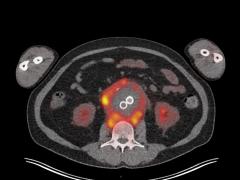

Een vrouw met afwijkingen rond een aorta-aneurysma